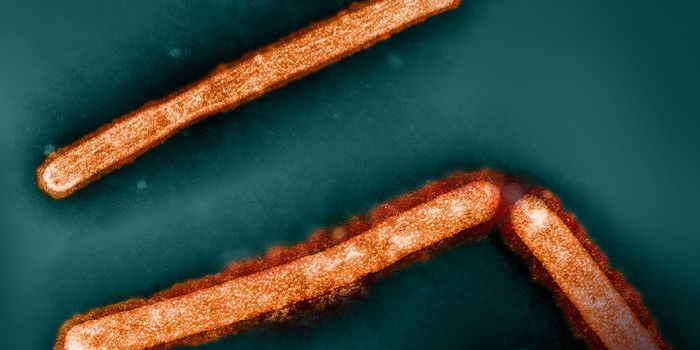

FEB 04, 2025Clinical & Molecular DXSudan virus (SUDV) can infect people to cause Sudan virus disease (SVD). Right now, an outbreak of SVD has been detected ...

FEB 03, 2025MicrobiologyThe highly pathogenic avian influenza H5N1 infection has killed millions of birds around the world, and has spread to hu ...

DEC 31, 2024Clinical & Molecular DXIn late November 2024, the World Health Organization was alerted to a serious public health crisis in a region of the Co ...

DEC 11, 2024Clinical & Molecular DXThe World Health Organization is investigating a mysterious illness now known as Disease X, which has sickened hundreds ...

NOV 24, 2024Clinical & Molecular DXAvian flu, particularly the highly pathogenic avian influenza H5N1, have caused huge amounts of wild and agricultural bi ...

NOV 19, 2024MicrobiologyOropouche virus (OROV) was first identified in a human patient in 1955 in a fevered charcoal worker on Trinidad, a ...